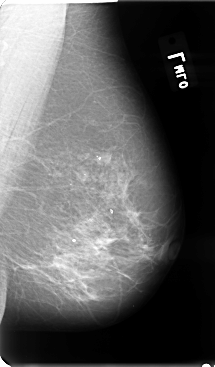

B_3075_1.RIGHT_MLO

RIGHT_MLO LINES 4792 PIXELS_PER_LINE 2880 BITS_PER_PIXEL 12 RESOLUTION 50 OVERLAY

FILE: B_3075_1.RIGHT_MLO.OVERLAY

TOTAL_ABNORMALITIES 3

ABNORMALITY 1

LESION_TYPE MASS SHAPE ARCHITECTURAL_DISTORTION MARGINS SPICULATED

ASSESSMENT 4

SUBTLETY 4

PATHOLOGY MALIGNANT

ABNORMALITY 2

LESION_TYPE CALCIFICATION TYPE PLEOMORPHIC DISTRIBUTION CLUSTERED

ABNORMALITY 3